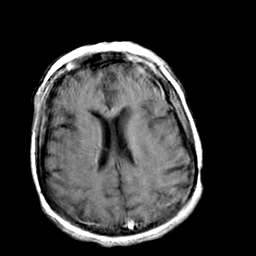

Creutzfeld-Jakob disease: gadolinium enchanced T1-Weighted MR -- Slice #15

[Home][Help][Clinical] Slice 15